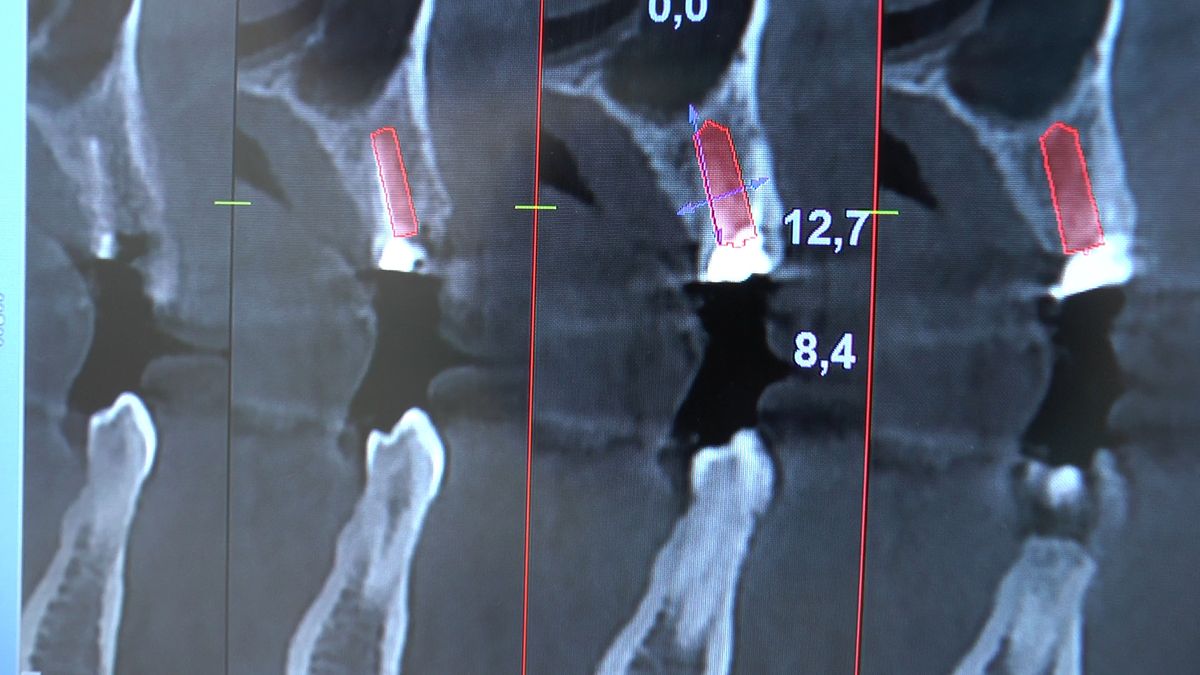

Pierwszy weekend 2019 roku w Instytucie Vivadental, to doskonałe otwarcie kolejnego roku edukacyjnego i szkolenia naszych Kursantów. W drodze do sukcesu w implantologii zdobywają wiedzę i umiejętności, a każdy kolejny zabieg to impuls i inspiracja do twórczego rozwoju w leczeniu własnych Pacjentów. Rozpoczęliśmy od sesji praktycznej implantologicznej właśnie z udziałem Pacjentów, na której dominowały samodzielne zabiegi wykonywane pod kierunkiem Mentorów – dr n.med. Violetty Szycik i dr n.med. Magdaleny Kisłowskiej – Syryczyńskiej. W ciągu dwóch dni zabiegowych przyjęliśmy 14 Pacjentów, przeprowadziliśmy zabiegi chirurgiczne, zabiegi regeneracyjne tkanki kostnej i augmentacji oraz wszczepiliśmy 20 implantów systemu Axiom. W ramach panelu edukacyjnego Sukces Twojego Biznesu odbyły się kolejne zajęcia z NLP, na których nasz Mentor Mariusz Wójcik z Gdańskiej Akademii Umiejętności Menedżerskich, kontynuował wprowadzenie do psychologii i podstaw kierujących decyzjami Pacjentów. Ćwiczenia w wesołej i koleżeńskiej atmosferze były niezwykle pouczające, a jednocześnie stanowiły idealną odskocznię po wyczerpujących zabiegach.